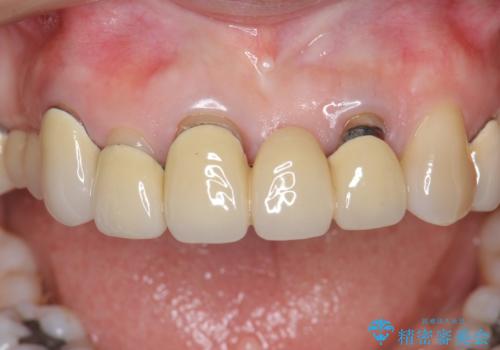

前歯ブリッジのやりかえ

- 前歯の審美障害、見た目の改善を希望され来院されました。

歯肉縁下カリエスも認められるため、挺出を行いセラミックブリッジを審美的に新製します。

- 47万円(仮歯×3・ファイバーコア×2・ジルコニアクラウン×3 歯の挺出)費用は治療当時の料金となります